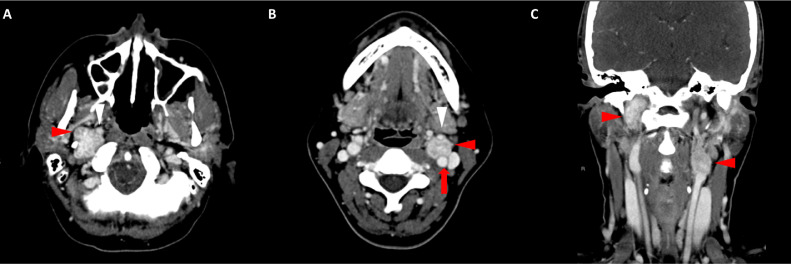

頸部增強(qiáng) CT 顯示 2 個(gè)強(qiáng)烈強(qiáng)化的腫塊。 一個(gè)位于頸部右側(cè),位于右側(cè)頸內(nèi)動(dòng)脈后方的頸動(dòng)脈間隙中,位于莖突內(nèi)側(cè),大小為 24 × 24 × 30 mm,頸靜脈橫向移位(圖 1A)。 第二個(gè)位于左側(cè)頸動(dòng)脈間隙,在分叉處正上方展開(kāi)頸外動(dòng)脈和頸內(nèi)動(dòng)脈,尺寸為 15 × 18 × 22 mm(圖 1B)。 影像學(xué)檢查結(jié)果與右側(cè)迷走神經(jīng)和左側(cè)頸動(dòng)脈體副神經(jīng)節(jié)瘤一致,與之前的活檢結(jié)果一致。

Fig. 1

圖1:右側(cè)迷走神經(jīng)和左側(cè)頸動(dòng)脈體副神經(jīng)節(jié)瘤。 (A) 軸位增強(qiáng) CT 顯示右側(cè)頸動(dòng)脈間隙、右側(cè)頸內(nèi)動(dòng)脈后方(白色箭頭)和莖突內(nèi)側(cè)有強(qiáng)烈強(qiáng)化的腫塊(紅色箭頭)。 (B) 軸位對(duì)比增強(qiáng) CT 顯示左頸動(dòng)脈間隙有強(qiáng)烈強(qiáng)化的腫塊(紅色箭頭),向后張開(kāi)頸內(nèi)動(dòng)脈(紅色箭頭),向前張開(kāi)頸外動(dòng)脈(紅色箭頭)。 (C) 冠狀對(duì)比增強(qiáng) CT 顯示兩個(gè)增強(qiáng)腫塊(紅色箭頭)。